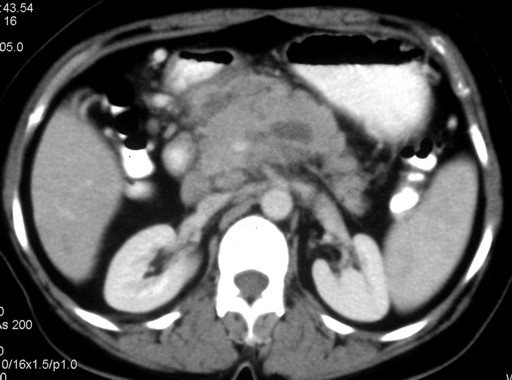

A 40-year-old female presented with abdominal pain of three months duration. The pain was located in the upper abdomen with radiation to the back. There were no exacerbating factors and the pain subsided with the ingestion of oral opioids. The patient also complained of weight and appetite loss. There was no history of alcohol ingestion. Her laboratory studies revealed an elevated erythrocyte sedimentation rate (46 mm in first hour; reference range: 0-20 mm) and were otherwise unremarkable. Serum amylase was 320 IU/L (reference range: 0-160 IU/L). A chest radiograph did not reveal any abnormality. Ultrasound of the abdomen did not reveal any abnormality and the pancreas was obscured by the bowel gases. Contrast-enhanced computerized tomography (CECT) of the abdomen demonstrated the bulky head and body of the pancreas with heterogeneous areas of non-enhancement suggestive of necrosis and peripancreatic fat stranding (Figure 1). The splenic vein was not visualized which was suggestive of thrombosis. The CECT findings were suggestive of focal pancreatitis involving the head and body of the pancreas with splenic vein thrombosis. As the patient had no history of severe pain which required admission, had ongoing chronic pain with loss of weight and appetite and a bulky head and body of the pancreas, image-guided fine needle aspiration was carried out to exclude a pancreatic malignancy. The cytological examination of the CT-guided fine needle aspiration revealed caseous necrosis. No acid-fast bacilli could be demonstrated. The Mantoux test was negative. However, a culture of the aspirated material demonstrated the growth of Mycobacterium tuberculosis. The patient was treated with anti-tubercular therapy for twelve months (four drugs for two months and two drugs for ten months). The patient improved with the therapy and was asymptomatic after completing two months of therapy. A repeat CECT of the abdomen performed after completion of the therapy revealed a normal pancreas with no focal lesions (Figure 2). The splenic vein was attenuated and collaterals were noted at perigastric, perisplenic and gastrohepatic locations (Figure 3). No varices were noted on upper gastrointestinal endoscopy. After four months of follow-up, the patient is asymptomatic.

Figure 1. Contrast-enhanced computerized tomography (CECT) showing the bulky head and body of the pancreas with heterogeneous areas of non-enhancement suggestive of necrosis and peripancreatic fat stranding. |